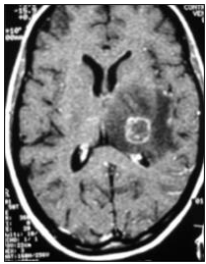

Uma paciente com 23 anos de idade foi admitida na emergência com quadro de crise convulsiva tônico-clônica generalizada. Sua mãe relatou que, nos últimos 15 dias, a paciente apresentou febre vespertina e cefaleia holocraniana. Procurou atendimento médico em duas ocasiões, nas quais foram prescritos apenas sintomáticos.

Ao exame, a paciente se encontrava emagrecida, hipocorada, desidratada, acianótica, anictérica, afebril, com dispneia e esforço respiratório. Candidíase oral e leões múltiplas por molusco contagioso em região genital. Diarreia. PA 90 x 55 mmHg, FC 110 bpm, FR 22 irpm, sat. O2 70. Gasometria revelou acidose metabólica. A paciente foi submetida à sedação, TOT e acoplada à VM. Toda medicação de suporte foi instituída, em especial a fenitoína venosa. Hemograma revelou anemia e linfopenia.

A imagem da tomografia de crânio com contraste revelou lesão anelar captante de contraste com edema perilesional e efeito de massa apagando parcialmente o ventrículo esquerdo e leve desvio da linha média.

O teste rápido para detecção do HIV foi reator. A mãe relatou que a paciente é alérgica à sulfa.

Baseado no relato, na imagem da tomografia computadorizada do crânio, e considerando a infecção oportunista neurológica grave mais comum na aids, assinale a opção que apresenta o diagnóstico e o tratamento específico mais indicado para o caso.

Ao exame, a paciente se encontrava emagrecida, hipocorada, desidratada, acianótica, anictérica, afebril, com dispneia e esforço respiratório. Candidíase oral e leões múltiplas por molusco contagioso em região genital. Diarreia. PA 90 x 55 mmHg, FC 110 bpm, FR 22 irpm, sat. O2 70. Gasometria revelou acidose metabólica. A paciente foi submetida à sedação, TOT e acoplada à VM. Toda medicação de suporte foi instituída, em especial a fenitoína venosa. Hemograma revelou anemia e linfopenia.

A imagem da tomografia de crânio com contraste revelou lesão anelar captante de contraste com edema perilesional e efeito de massa apagando parcialmente o ventrículo esquerdo e leve desvio da linha média.

O teste rápido para detecção do HIV foi reator. A mãe relatou que a paciente é alérgica à sulfa.

Baseado no relato, na imagem da tomografia computadorizada do crânio, e considerando a infecção oportunista neurológica grave mais comum na aids, assinale a opção que apresenta o diagnóstico e o tratamento específico mais indicado para o caso.